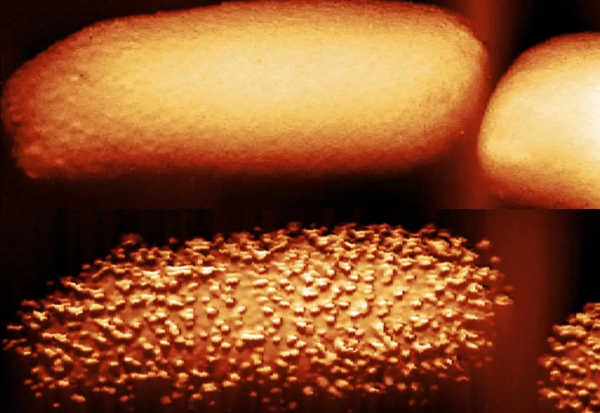

Фото: Nature Microbiology

Користејќи биохемиски тестови и атомски силен микроскоп, метода во која игла со големина од нанометар ја мапира површината на клетката, Едвардс и неговиот тим забележале дека полимиксинот B предизвикува испупчување на површината на бактеријата ешерихија коли. Неколку минути подоцна, бактериите го исфрлаат липополисахаридот. Во процесот, бактериите се обидуваат да ги надоместат изгубените липополисахариди со додавање нови.

- Антибиотиците се како сила што помага „тулите“ да излезат од ѕидот. Надворешната мембрана не се распаѓа и не отпаѓа, но очигледно постојат празнини низ кои антибиотикот може да стигне до другата мембрана - објаснува Едвардс.